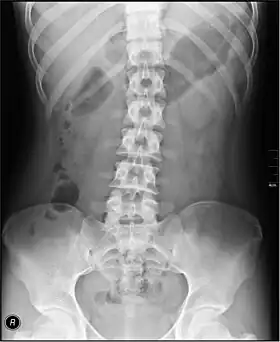

The standard abdominal X-ray protocol is usually a single anteroposterior projection in supine position.[15] A Kidneys, Ureters, and Bladder projection (KUB) is an anteroposterior abdominal projection that covers the levels of the urinary system, but does not necessarily include the diaphragm.

- The spine (that is, the vertebral column. A projectional radiograph of the spine confers an effective dose of approximately 1.5 mSv, comparable to a background radiation equivalent time of 6 months.

- Lumbar Spine - AP and Lateral +/- L5/S1 view in the UK, with obliques and Flexion and Extension requests being rare.[15] In the US, basic projections include an AP, two Obliques, a Lateral, and a Lateral L5-S1 spot to better visualize the L5-S1 interspace. Special projections are AP Right and Left bending, and Laterals with Flexion and Extension.

- Pelvis - AP only in the UK, with SIJ projections (prone) on special request.[15]